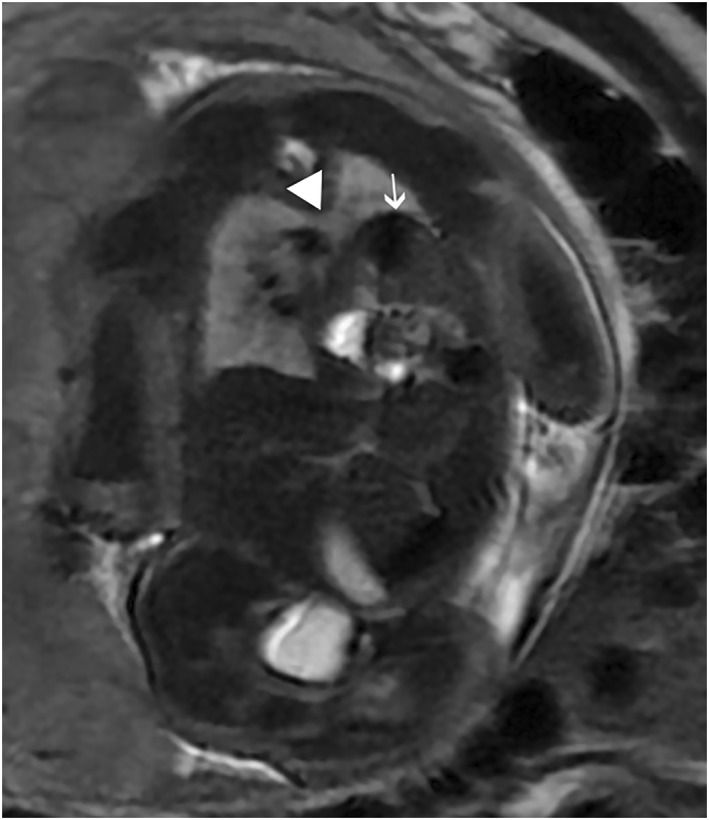

Results: One case was diagnosed by magnetic resonance imaging (MRI) and two by ultrasound with MRI confirmation. Two patients were referred to our center for diaphragmatic hernia (with a sac in one case). The third patient was referred because of a thoracic aorta on the very left side. After birth, costal anomalies, agenesis of the body and tail of the pancreas, and an associated pelvic kidney were diagnosed. All neonates were presented with acute respiratory distress; two had a favorable outcome, and the third died within the first few days of life.